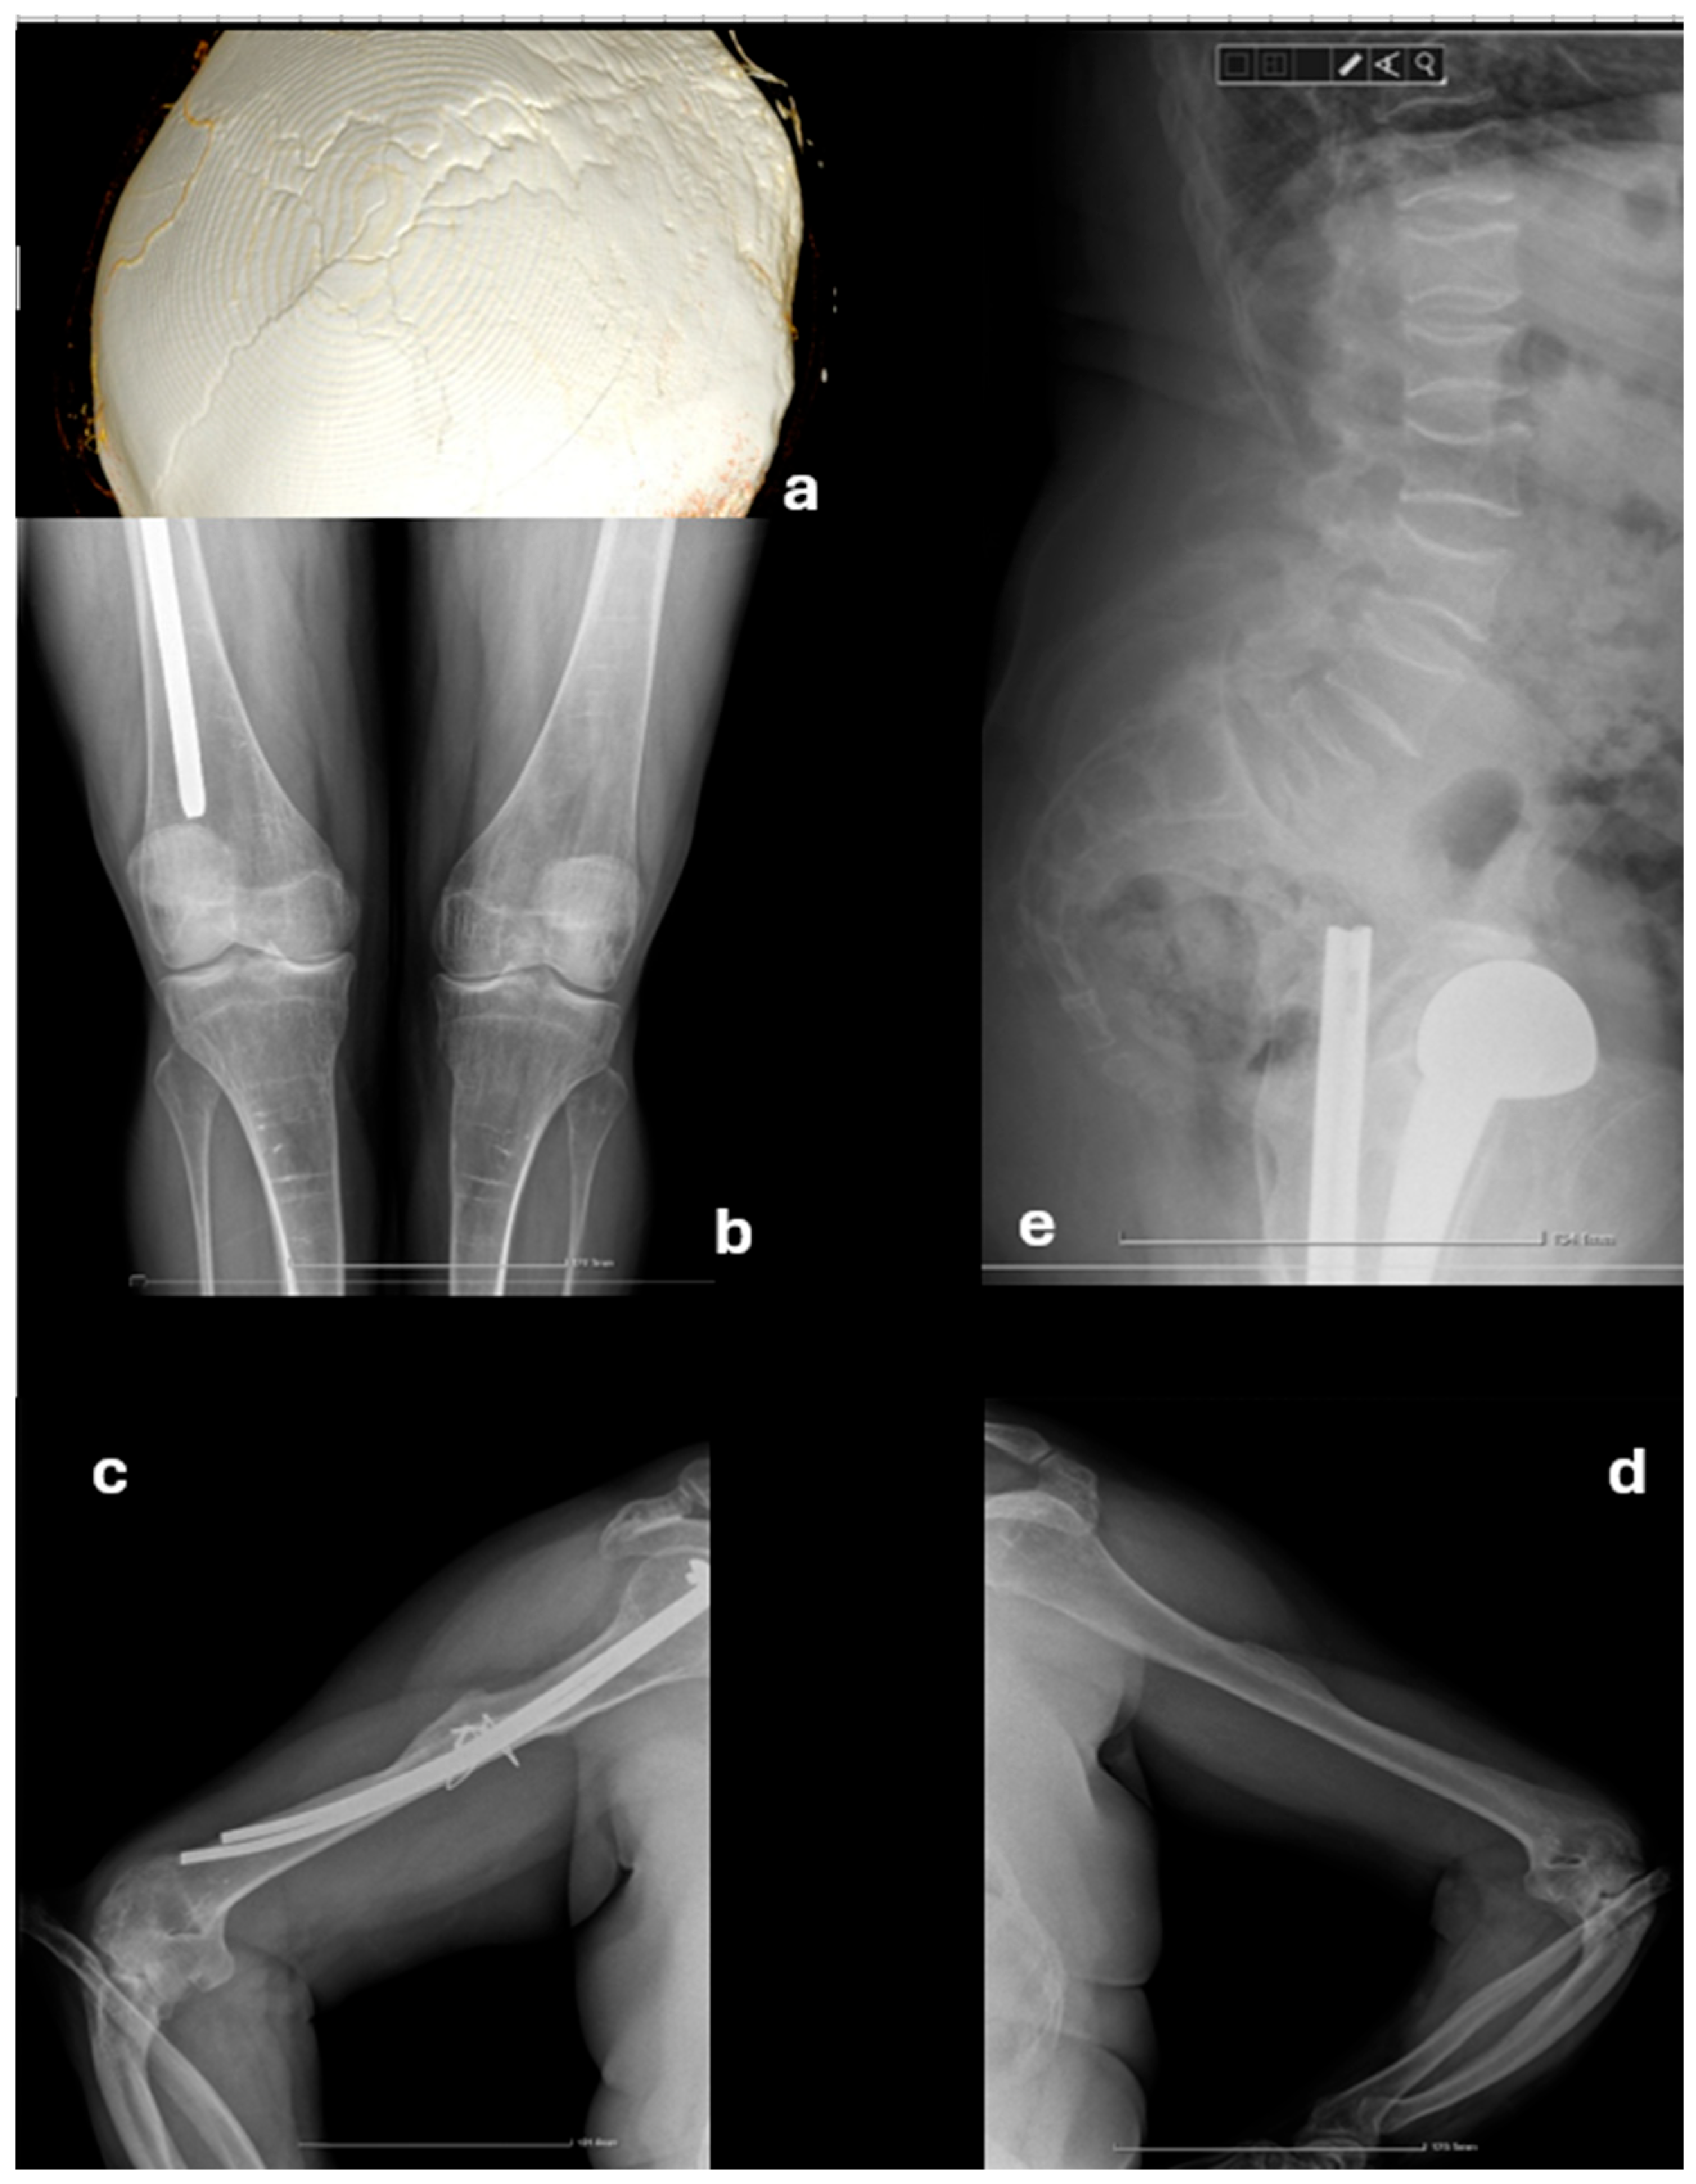

2. Case Presentation

2.1. Initial Presentation

2.2. Further Investigations

2.3. Management and Follow-Up